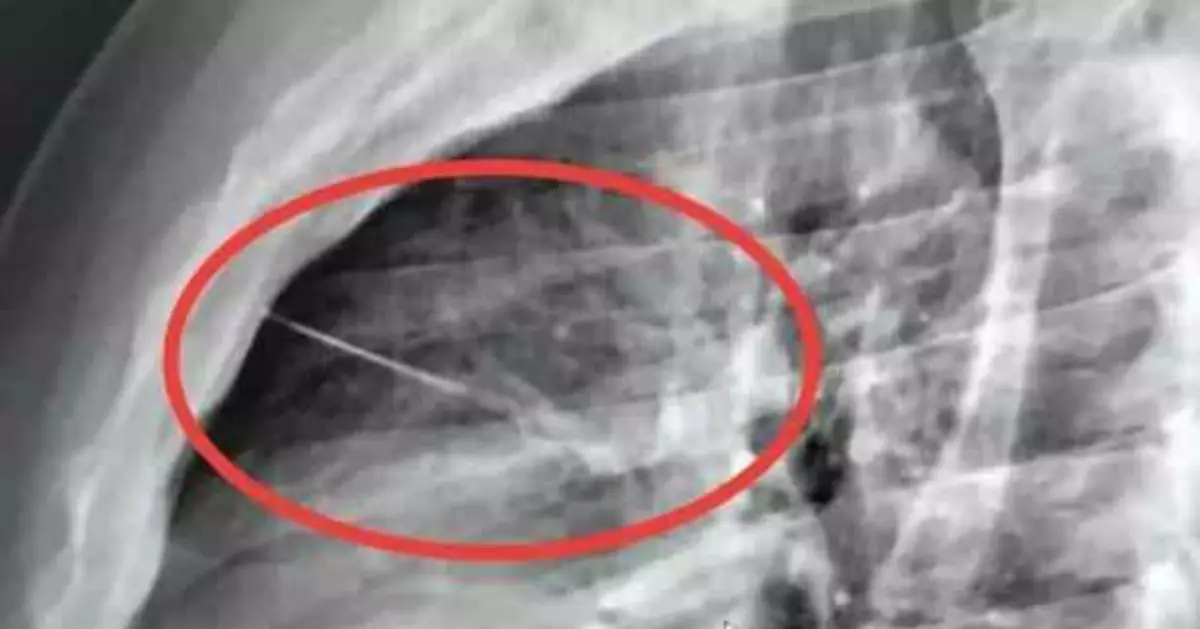

泰國一名男子返工回家後躺床後胸痛難耐,被送院照X光驚揭7CM縫衣針插入胸腔,險刺穿心臟。

X光揭心臟旁藏7釐米縫衣針 情況危急需轉院

救援人員進行初步檢查時,並未在布隆勒特身上發現任何傷口,於是先將他送往克拉桑醫院接受詳細檢查。直至院方安排X光檢查後,才赫然發現布隆勒特心臟附近卡有一件細小尖銳異物,之後證實為一根約7CM長的縫衣針。位置緊貼心臟,險些刺穿心臟,情況相當危急。由於異物所在位置極其危險,手術難度及風險均相當高,院方隨即決定將他轉送武里南醫院準備施手術。